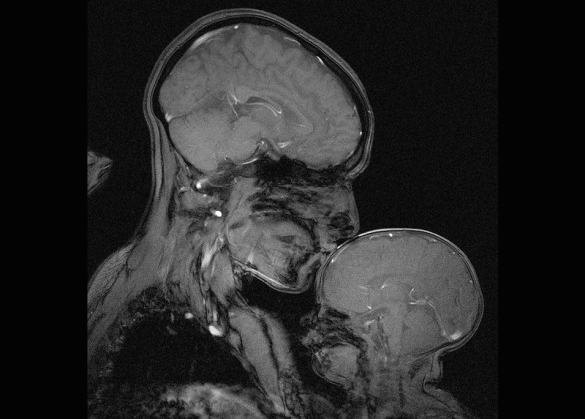

Mama si Copilul. Iubirea materna prin ochii stiintei

Rebecca Saxe, neurolog la MIT, a capturat aceasta imagine uimitoare realizata cu ajutorul unui aparat RMN 3 Tesla, creand o lucrare de arta abstracta emotionanta, scrie gizmodo.co.